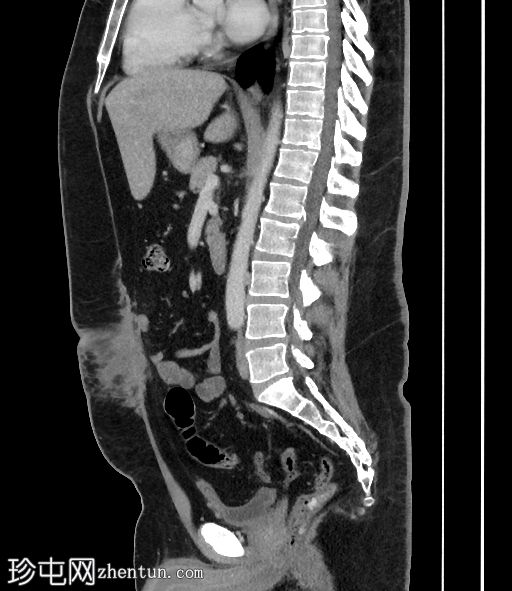

轴向C+门静脉期

矢状C+门静脉期

肝脏脂肪变性,伴地图样脂肪沉积。胆囊扩张,胆囊壁增厚,周围浑浊,胆囊颈结石,胆囊前壁凹陷(胆底张力征)。

本病例展示了CT扫描在急性胆囊炎(通常是意外诊断)诊断中的价值。CT扫描通常比

检查更具评估价值,因为能够更准确地识别脂肪条带。胆囊底张力征提示胆囊受阻并承受压力,因为它会凹陷(而不是顺应)前腹壁。